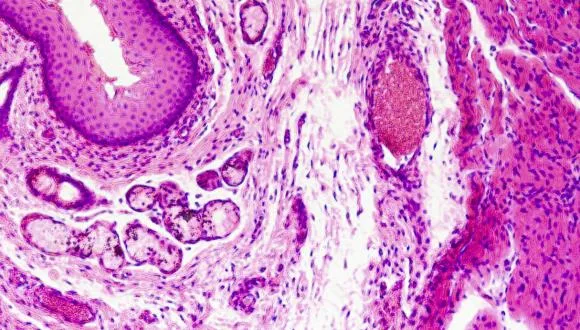

לאחרונה, חלה תפנית בהבנת הבסיס לתופעות אלרגיות. חוקרים רבים גורסים כעת כי ההפרעה בתפקוד מערכת החיסון במחלות אלה משנית לפגם ראשוני במבנה המחסום העורי. מחסום זה ממוקם בשכבות העליונות של העור ואחראי על שמירת מרכיבים חיוניים בעור, ומניעת כניסתם של גורמים חיצוניים מזיקים, כולל כאלה המסוגלים לעורר תגובה חיסונית לקויה. תוצאות המחקר מספקות כעת הוכחה חותכת לסברה זו, מה שצפוי להוביל לשינוי בגישה לפיתוח תרופות חדשות לתופעות אלרגיות.

ד"ר ליאת סמואלוב אשר הובילה יחד עם ד"ר עופר שריג את המחקר במרכז הרפואי תל-אביב, מציינת: "הדזמוזומים אחראים על הצמדת תאי העור זה לזה. מצאנו כי מרכיב חשוב של הדזמוזומים בשם דזמוגלאין 1 חסר בעורם של חולים הלוקים במחלה בשם תסמונת SAM, הבאה לידי ביטוי בתגובה עורית אלרגית קשה". שריג מוסיף: "המחלה נגרמת כתוצאה מהפרעה בבניית קשרים בין תאיים בשכבות העליונות של העור, מה שמאפשר לחלבונים שונים לחדור דרך העור ולעורר תגובה חיסונית מופרזת. המעניין אף יותר הוא שכשנבדקו במעבדה תאים שהופקו מעור החולים, נמצא שתאים אלה מפרישים עצמונית מגוון מתווכים של התגובה האלרגית. במובן זה, תוצאותינו מעלות שאלות לגבי תפקידה הראשוני של מערכת החיסון בגרימת אלרגיה, מה שכמובן צפוי להצביע על אסטרטגיות טיפוליות חדשות בדלקת עור אטופית ותופעות אלרגיות אחרות".